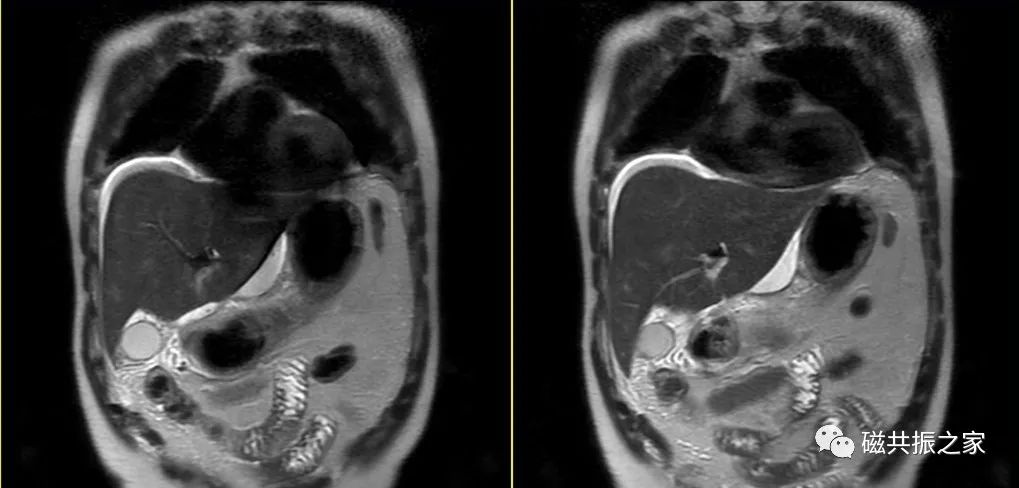

冠状面:冠状面稳态自由进动序列/单次激发T2WI序列。

在横轴位和矢状位定位,扫描范围包括肝脏前后缘,合理调整扫描范围,需包括整个病变范围。

上腹部的扫描应首先扫描范围较大的冠状面图像,以便对病变及周围组织器官作出大体地评估,更有利于精准地定位和扫描方案的制定。

冠状位:冠状位平衡期/延迟期增强补充序列

在横轴位及矢状位上定位,范围包括整个肝脏及病变范围。

大范围的冠状位增强序列有助于对血管、胆管、十二指肠区域以及周围受累情况的评估,